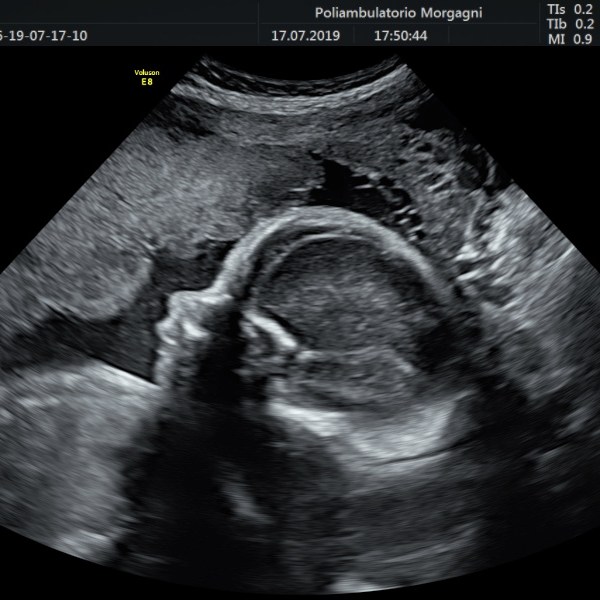

Il mese si conclude con l’ecografia di accrescimento da non eseguire troppo precocemente per ridurre il lasso di tempo fino al momento del parto.

Oltre la valutazione della biometria fetale, è importante controllare il benessere fetale con flussimetria a livello del cordone ombelicale e la quantità di liquido amniotico, vera cartina di tornasole del benessere fetale.